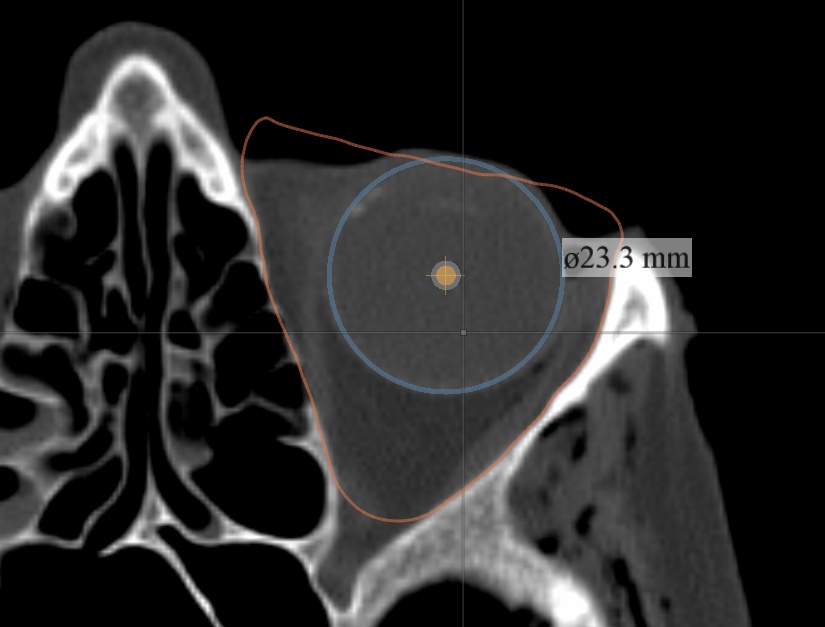

Stratovan Maxillo™ computes orbit (eye socket) volumes and bony contour shapes directly from x-ray computed tomography (CT) image data. Maxillo is intended for research use only by otolaryngologists, ENTs, plastic, and maxillofacial researchers investigating orbit morphology, shape, volume, and globe position. Maxillo utilizes a patent-pending image segmentation method.